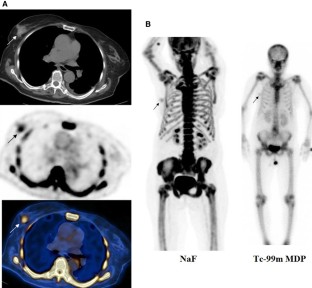

NaF positron emission tomography/computed tomography (PET/CT) images of 69 newly diagnosed breast cancer patients were reviewed. F-18 fluoride uptake as maximum standardized uptake value (NaF SUVmax) was measured in the primary tumor, enlarged axillary lymph nodes and contralateral normal/non-tumoral breast tissue. Low-dose CT images were reviewed to locate the primary tumor and grossly assess its calcification and check for ipsilateral axillary lymphadenopathy. Whole body NaF PET/CT images were reviewed to search for bone metastases. Eighteen patients also underwent F-18 fluorodeoxyglucose (FDG) PET/CT study.

Results

The primary breast tumor was clearly seen as focal or diffuse uptake on NaF PET images in 27 of 69 patients (39%) (mean NaF SUVmax: 2.0 ± 1.0). In the rest, there was only mild bilateral diffuse breast uptake. When analyzing images per histological subtype (42 patients, 43 tumors), 14 of 31 invasive ductal carcinomas (IDC) (45%) and 3 of 4 ductal carcinoma in situ (DCIS) were visible on PET. Five invasive lobular carcinomas, 2 invasive mammary carcinomas, and 1 mucinous carcinoma were not visible on PET. Mean NaF SUVmax of contralateral normal/non-tumoral breast tissue was 1.0 ± 0.4. There was no significant difference in mean NaF SUVmax of primary tumor in cases with and without calcification or with and without axillary lymphadenopathy (p 0.892 and 0.957). There was no correlation between NaF SUVmax and FDG SUVmax values of the primary tumors (r 0.072, p 0.797, Pearson correlation).